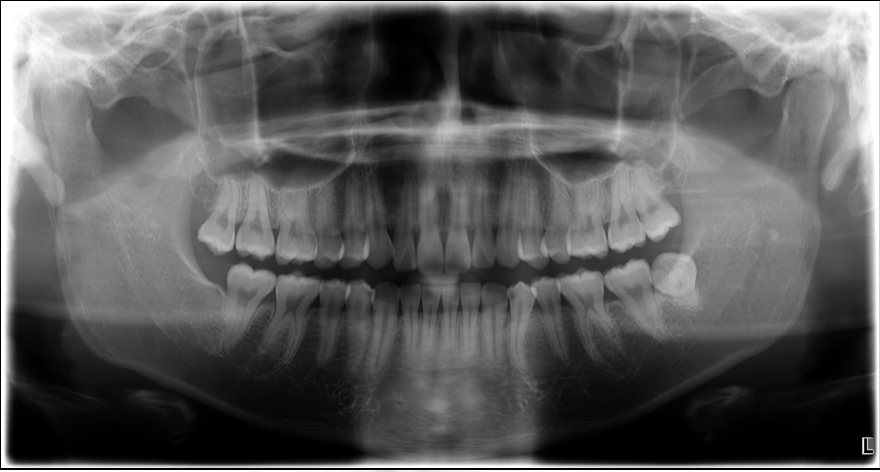

治療前

親知らずの抜歯というと「痛そう」「腫れそう」「怖い」

そんなイメージをお持ちの方も多いのではないでしょうか?

実際、親知らずの抜歯後に顔が腫れたり、痛みや出血でつらい思いをされたという声も耳にします。

ですがご安心ください。

池袋にあるグランドメゾンデンタルクリニックでは、日本口腔外科学会認定医による、安全で身体に優しい親知らず抜歯を行っております。

今回は、当院の親知らず抜歯に対するこだわりや、術後のダメージを最小限に抑えるポイントについてご紹介します。